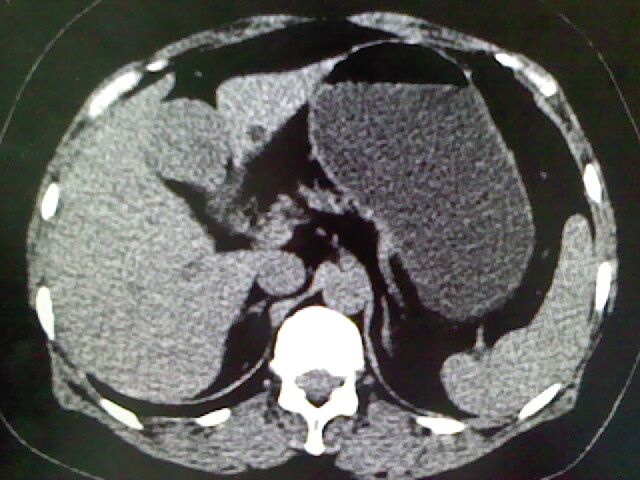

以下是引用卜一在2009-4-2 13:26:00的发言:[br]胆囊颈部结石伴胆囊炎!另:建议增强,待除外肝内占位及胆囊占位!

以下是引用liaoqiang在2009-4-2 16:23:00的发言:[br]胆囊是否切除?胆囊颈区致密影考虑金属夹?结石?肝脏右叶低密度影,考虑增强。